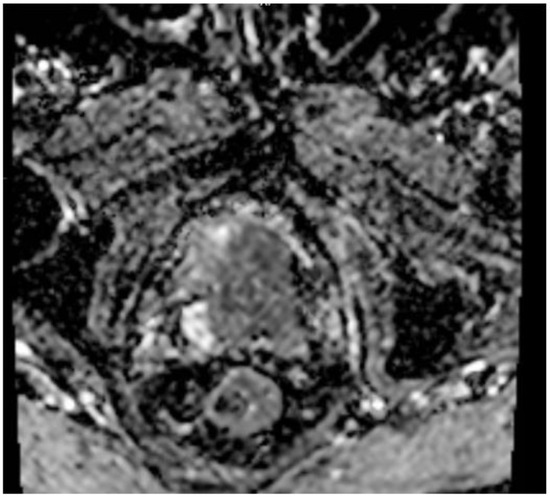

A 77-year-old man presented with several weeks of exertional dyspnea and intermittent dry cough. His past medical history was notable for ankylosing spondylitis, chronic gastritis, a left salivary gland tumor resected 11 years prior (pathologic details unknown), and a cholecystectomy. He had a significant smoking history (20 pack-years) but quit 32 years earlier. An initial chest radiograph, obtained to evaluate possible heart failure, revealed a large right-sided pleural effusion. Figure 1 A contrast-enhanced computed tomography (CT) of the chest further delineated multiple pleural nodules (up to 17 mm) and diffuse, bilateral small pulmonary nodules. Figure 2 and Figure 3 Two thoracenteses drained ~3800 mL of hemorrhagic pleural fluid in total. Fluid cytology was negative for malignancy, and no cell block preparation was performed. Further evaluation with bronchoscopy and bronchoalveolar lavage was unremarkable for infection or malignant cells.

Figure 6. MR—diffusion-weighted imaging 2000, axial plane, hyperintense lesion indicating restricted diffusion is observed.

Figure 7. MR—ADC map. On the corresponding ADC map, the lesion appears hypointense.